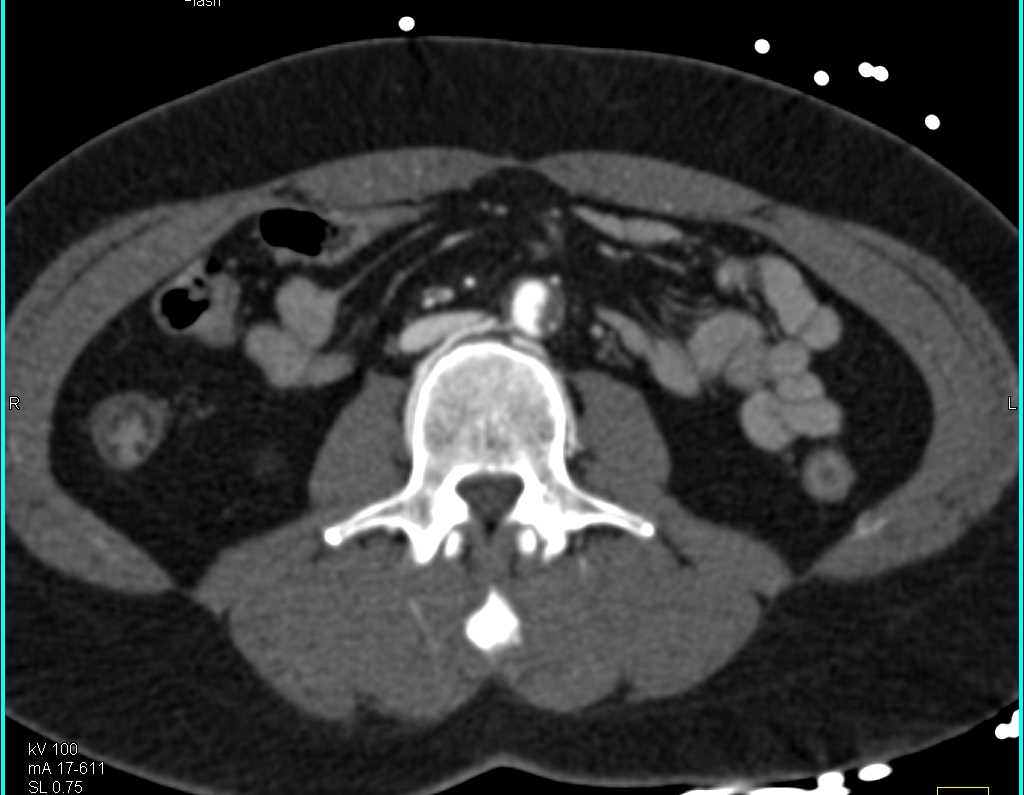

Diagnosis

Bronchial Artery Aneurysms